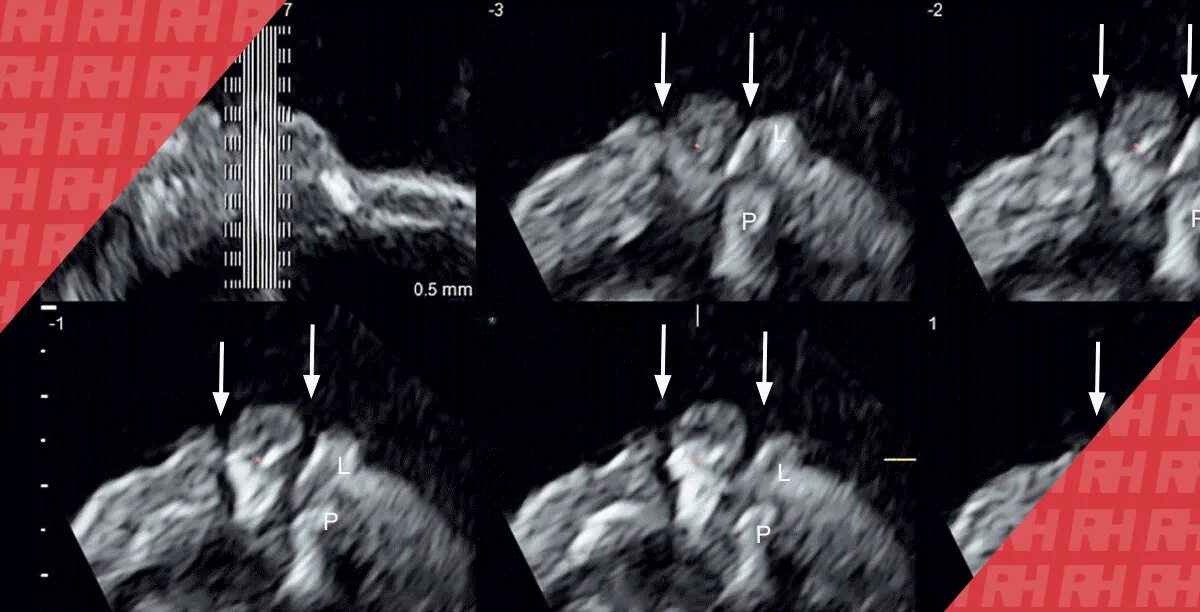

Узи аномалий